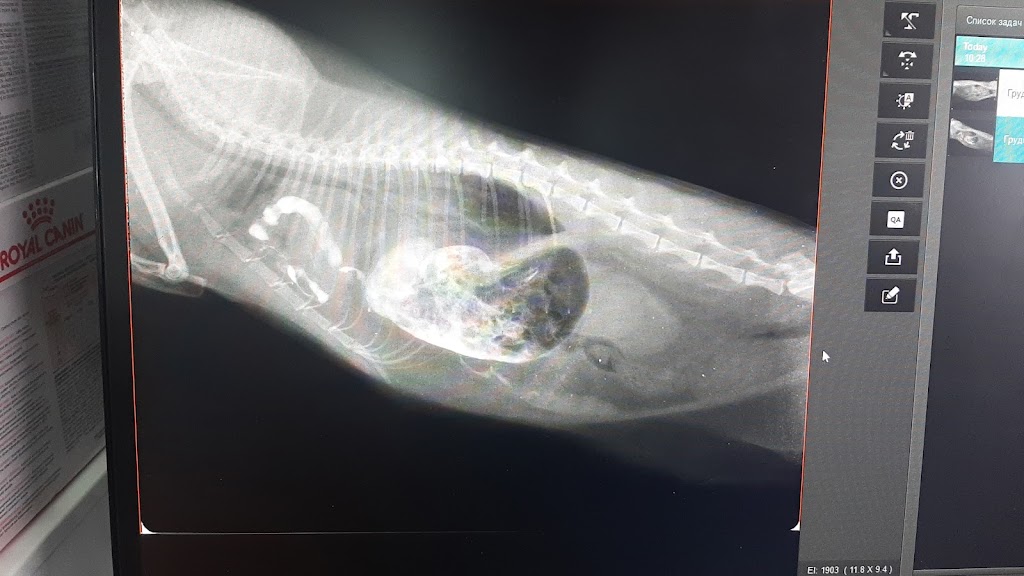

Ветеринарна лікарня “Ковчег” у Олександрії — це клініка з теплим ставленням і потужною діагностикою. Пацієнти відзначають ретельні аналізи, грамотні призначення та успішні операції з подальшою реабілітацією; багато власників повертаються як постійні клієнти. Тут працюють уважні й ввічливі лікарі, доступні ціни та прозора оплата за прийом. Якщо шукаєте надійну допомогу для улюбленця в місті — це місце варте довіри.